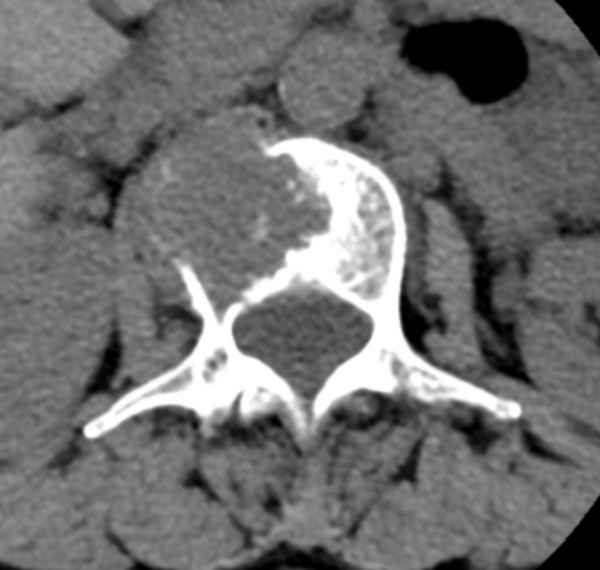

△ 術(shù)前CT:腰2椎體骨質(zhì)破壞,伴周圍軟組織腫脹,考慮骨轉(zhuǎn)移瘤。